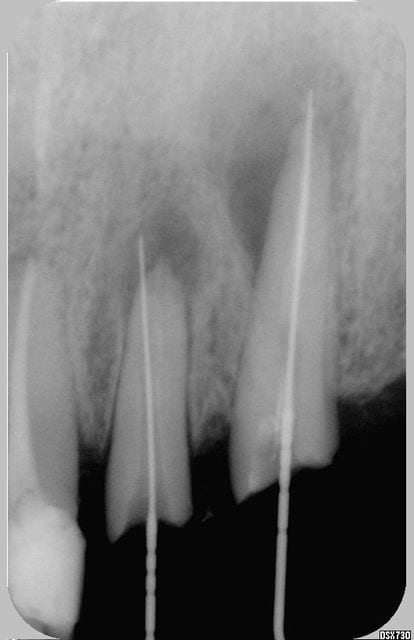

4 ans après ubigtx - Eugenol

Franchement beau resultat la...

je viens de voir votre post et vous mets une réponse en ligne avec quelques radios preop, postop, à 4 ans après et je vous dirai ce que j'ai mis pour obtenir ce résultat satisfaisant il me semble, par ailleurs vous me direz si en toute impartialité vous auriez opté pour la même option de tt ou si vous n'auriez pas fait l'exo et implanto.

à vous lire....